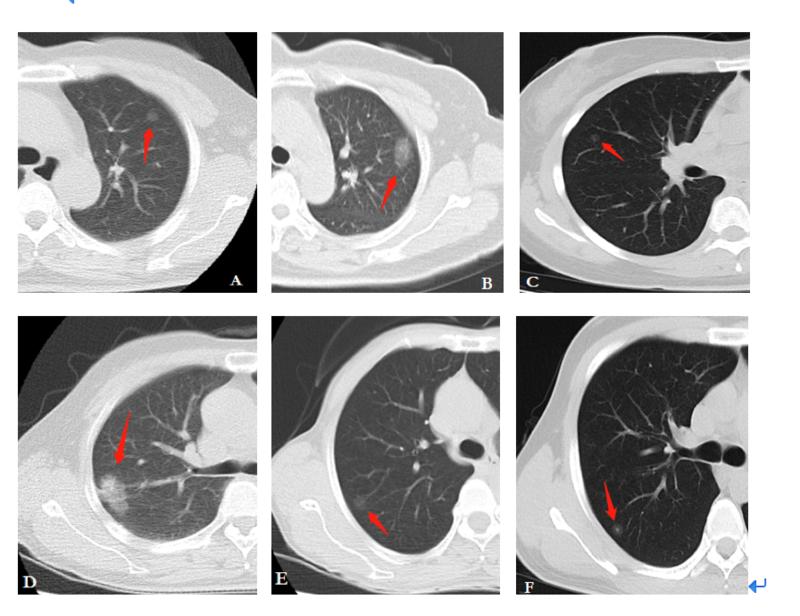

真假支气管爬行征肺腺癌1例ct影像讨论

早期肺癌ct图影像

早期肺癌ct图图解

肺癌ct图片图解

早期肺癌ct图